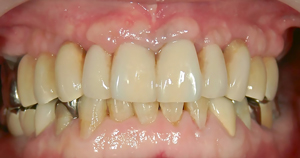

これは、上あご全てにインプラント治療を終えられた60代男性の写真です。

「上の入れ歯をインプラントにかえたい。出来るなら、費用は抑えて、丈夫で長持ちさせて欲しい」

これが、この患者様のインプラント治療に対する希望内容でした。

実際、上あごには御自身の歯は1本も残っておらず、総入れ歯が装着されていました。そこで、5本のインプラントを上あごに埋入して土台を作り、セラミック歯の12本(連続)を5本のインプラントにネジで固定しました。